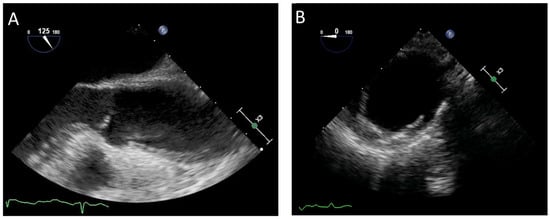

IMH is classified among AAS and represents about 15% of cases. Specifically, it is defined as Type A when it affects the ascending aorta and the aortic arch and type B when it involves the descending aorta. [5]. Echocardiography is a useful method for diagnosing IMH, preferably with TOE due the low sensitivity of TTE (<40%) [40]. IMH is typically diagnosed in the presence of crescentic or concentric thickening of the aortic wall > 0.5 cm [41]. Furthermore, it is characterized by the absence of intimal tear, mobile dissection flap, and Doppler signal indicating a communication between the aortic lumen and hematoma. The luminal shape is preserved and the luminal wall is curvilinear and smooth. Other secondary findings are the presence of intimal calcification displacement and echo-lucent areas in the aortic wall hematoma (Figure 2A) [2]. Complications due to IMH cover a broad spectrum. Indeed, hematoma can evolve towards classical or localized AD, saccular or fusiform dilatation, pseudoaneurysm, or aortic rupture in the pericardium, pleura, or mediastinum [42]. Limitations in using the TOE in this setting include the limited visualization of all segments of the aorta, semi-invasive nature, and operator dependency. In several situations, diagnosing IMH can be challenging. Indeed, classical AD with thrombosed false lumen may be similar to IMH, but the diameter is generally larger and the circumferential extension is smaller. Instead, aortic atherosclerosis and aortic aneurysm with mural thrombus differ mainly in the presence of an irregular luminal surface. Furthermore, intimal calcification displacement is useful for further differentiation and characterization. Finally, a hemizygous sheath is also considered in the differential diagnosis with IMH. This is a normal structure, a periaortic fat pad situated 30–35 cm from the incisors during TOE [43].

Figure 2.

Transesophageal echocardiography assessment in two different patients with acute aortic syndrome: (A) intramural hematoma and (B) penetrating aortic ulcer.

4.1. Transesophageal Echocardiography

TOE is among the methods for detecting PAU and evaluating possible complications (Figure 2B). Although it could be situated in any segment of the aorta, PAU is infrequently located in the ascending aorta, aortic arch, and abdominal aorta, while it is more commonly present in the mid and distal segments of the descending aorta [5]. The key diagnostic feature is the presence of a crater-like out-pouching with jagged edges of the aortic wall and multiple irregularities of the intimal wall. Color Doppler can be useful for describing turbulent flow within and at the entrance orifice of the ulcer. This method ensures the excellent visualization of the aortic wall and provides maximum depth of ulcer penetration from the aortic lumen. In addition, the location, width, and length of the ulcer and aortic diameter at the level of the PAU may also be detected [2]. Localized IMH is generally associated with the lesion and could involve the rest of the aorta [53]. The diagnostic value of the TOE is moderate and the use is restricted by the semi-invasive nature. Echocardiography can detect complications associated with PAU. Acute AD, pseudoaneurysm, or rupture of the aorta could result from the propagation of ulcer erosion [54]. Furthermore, PAU can evolve towards the formation of a saccular, fusiform, or false aneurysm. Finally, TOE has the capacity to differentiate PAU from an ulcer-like projection (ULP). Specifically, ULP is a localized pouch with a large communication orifice protruding generally in the IMH.